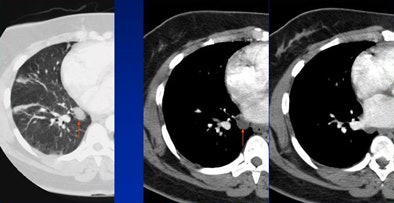

|  |

| False-positive: Hypertrophic costochondral junction misread as a lung mass. |